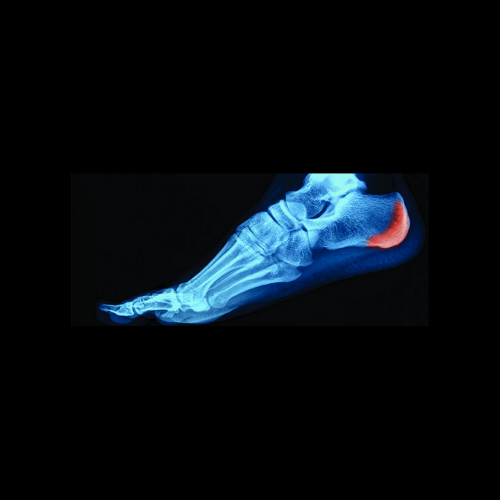

Espolón Carlcáneo

Es un crecimiento, prominencia que aparece en la parte anterior al talón que tiene una forma de lanza, ésta situación va tensando las zonas blandas alrededor provocando grandes dolores a través de una patología llamada fascitis plantar, dificultando el apoyo del talón y llegando hasta inflamaciones en el pie.

La tensión suele tratarse con éxito con la Plantillas Foot Global, las que van aliviando la tensión haciendo que la zona sea más cómoda al caminar.